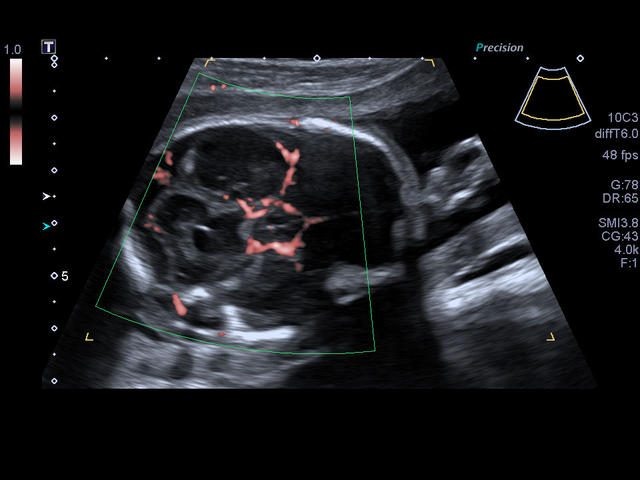

Xario 200 — это продуманная эргономика, впечатляющее качество изображения, отлаженный рабочий процесс и предельно высокая компактность. В Xario 200 цветовая доплеровская визуализация вышла на качественно новый уровень. Полностью интегрированная система управления данными пациентов и изображениями системы Xario обеспечивает удобный просмотр и простое управление исследованиями.

- Акушерство

- Автоматическое измерение воротникового пространства (Auto NT).

- Автоматическое измерение ТВП плода в режиме 2D: NT